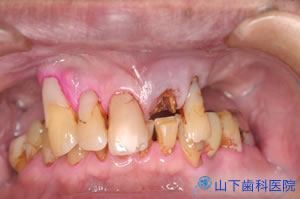

| 「入れ歯」では思うように噛めず、気持ち悪い。前歯で噛んでいるがぐらぐらしてきた。 残る歯もすっきりしない所が多々あり、今後に不安を抱えて来院されました。 |

| 初診時のレントゲン写真です。 | ![]() |

| 上下の奥歯が咬み合うことで決まる咬合が不安定で、下の前歯が上の前歯を突き上げています。 予知性がない右下、左上の4番目を抜歯して落ち着いた状態です。 |